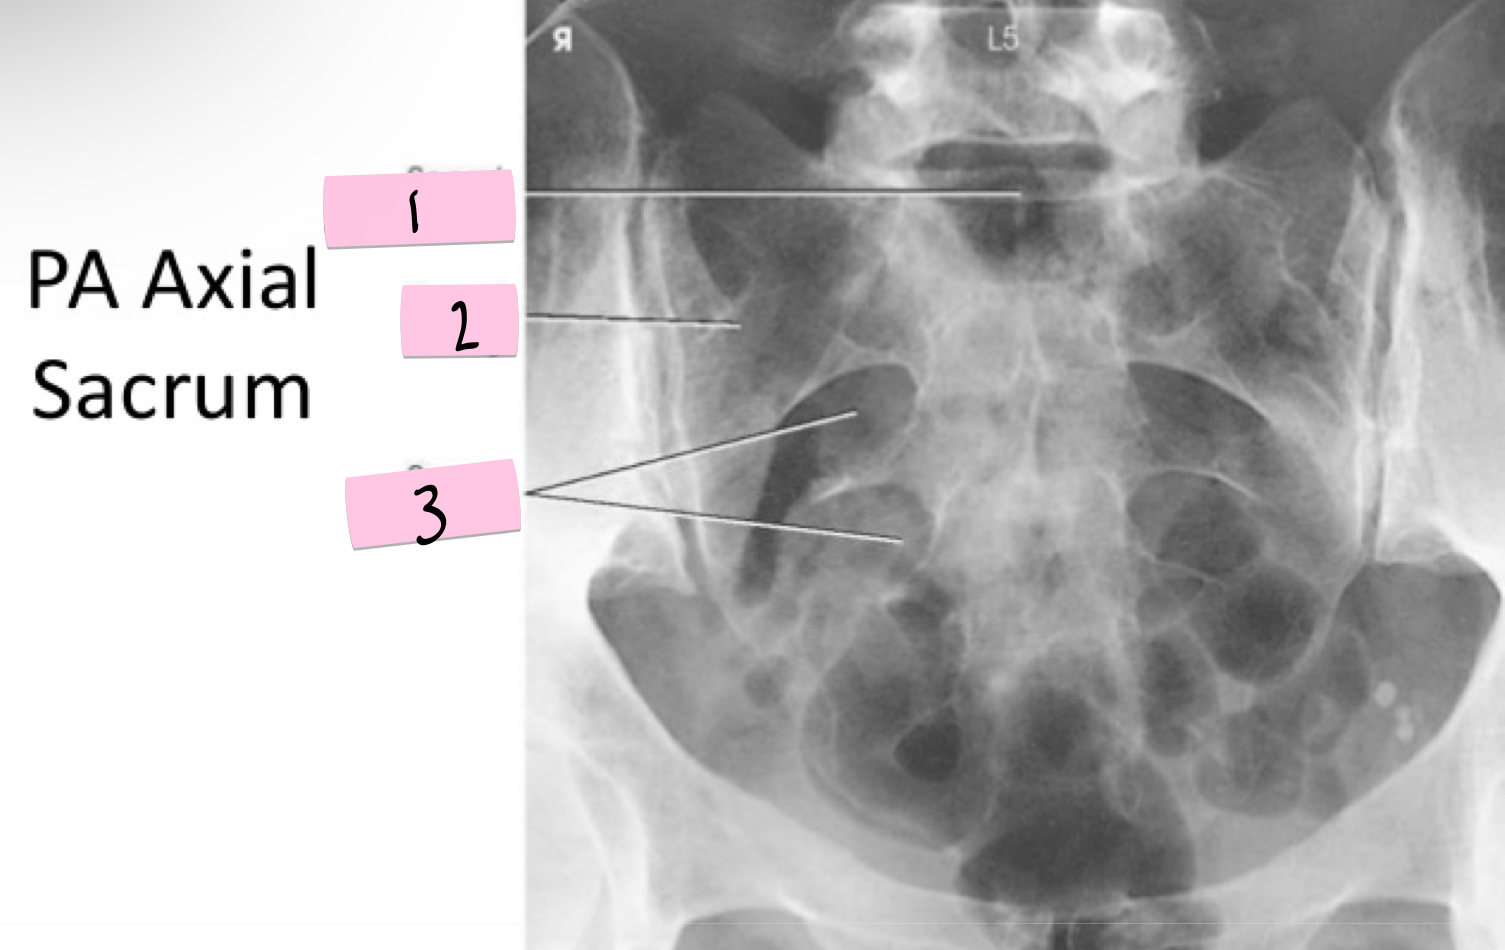

What is 1 pointing to?

Sacral promontory

What is 2 pointing to?

Sacral wing

What is 3 pointing to?

Sacral foramina